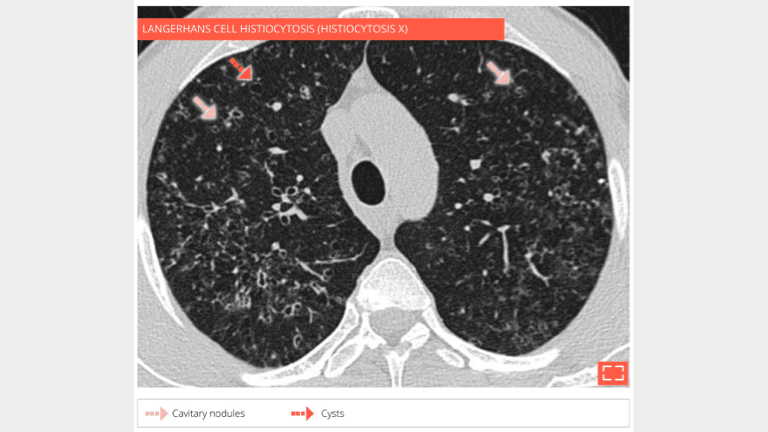

HRCT at the level of the upper lobes shows numerous micronodules, cavitated nodules, and cysts in a 32-year-old man curent smoker who developed langerhans cell histiocytosis.